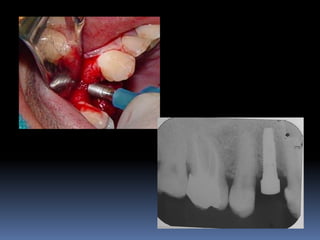

Exames Imaginológicos

Radiografias periapicais, telerradiografias e

panorâmicas;

Tomografias computadorizadas

Softwares de imagens 3D